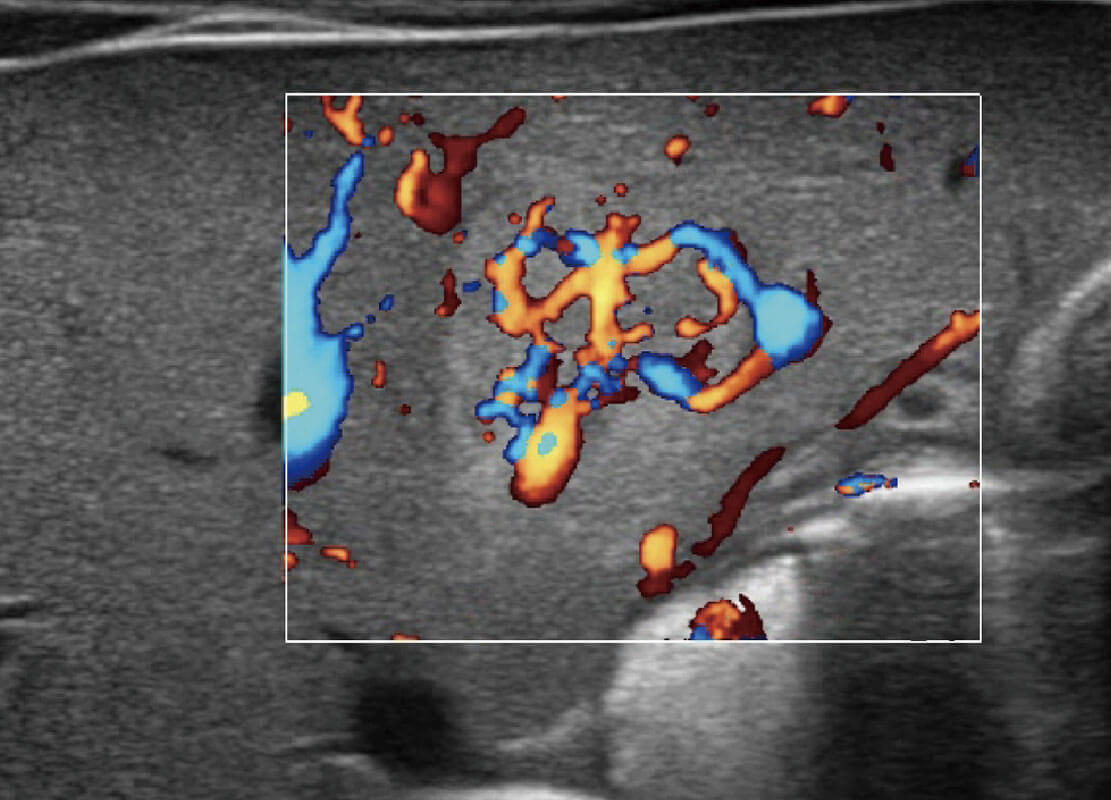

新生儿肝血管癌

P60搭载宽频带线阵探头、宽景成像、弹性成像技术,为您提供乳腺应用方案。P60支持高频相控阵探头、线阵探头、腹部高频探头、腹部微凸探头等,丰富的探头群搭载敏感的彩色血流成像,适用于新生儿多种脏器检测要求,满足新生儿筛查需求。